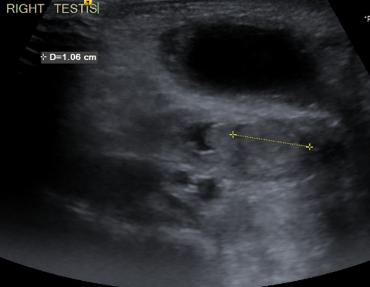

Intrauterine testicular torsion: A case report

Introduction: Intrauterine testicular torsion is a relatively rare but serious entity of the neonatal period. It is often diagnosed at birth or within the first hours of life, while prenatal detection remains challenging. Timely diagnosis and management undoubtedly pose a significant challenge for the pediatrician.

Method: We describe a case of a full-term male neonate, with normal prenatal ultrasound findings, born with a prominent swelling in the right inguinal region without signs of local inflammation. Further investigation was performed with a scrotal and inguinal ultrasound.

Results: The ultrasound findings were more consistent with a right spermatic cord cyst, with a suspicion of micro-rupture. This finding was considered extremely rare by pediatric surgeons for a newborn. Since intrauterine testicular torsion could not be ruled out despite the inconsistent ultrasound, the young patient was immediately therefore referred to a pediatric surgical clinic, where testicular torsion was diagnosed. As the testis maintained some degree of perfusion, bilateral orchiopexy was performed.

Discussion: Intrauterine testicular torsion is usually diagnosed after birth, when the damage to the testis is already irreversible. The painless clinical presentation may lead to a delayed diagnosis, while Doppler ultrasound, although useful, should not delay surgical exploration in suspicious cases. Despite the low probability of salvaging the affected testis, surgical intervention is essential to confirm the diagnosis and prevent contralateral torsion through prophylactic orchiopexy. Early recognition by the pediatrician and prompt collaboration with the pediatric surgeon are crucial for the optimal management of this rare neonatal condition.